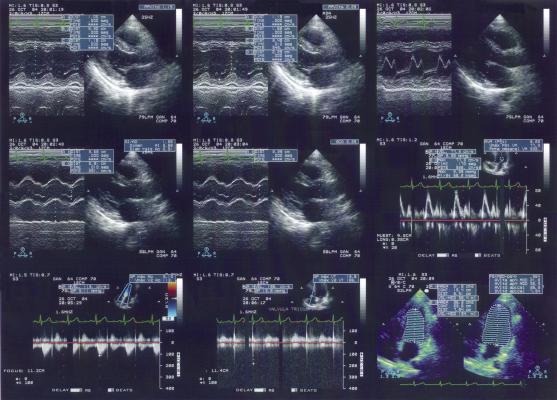

December 9, 2015 — ContextVision AB announced the development of a prototype technology that enables ultrasound imaging to be automatically optimized for each patient. The concept was demonstrated to a few select potential customers during the 2015 annual meeting of the Radiological Society of North America (RSNA), Nov. 29-Dec. 3 in Chicago.

The use of ultrasound for diagnostics and guidance during treatment is growing. An increasing number of patients represent challenges for accurate ultrasound imaging, due to obesity, excessive muscle mass or age-related diseases. Providing accurate ultrasound images of these patient groups can be difficult and time-consuming. Automated adjustment into the optimal image quality will increase diagnostic accuracy and save time.

ContextVision’s new prototype VEPiO (Virtual Expert Personal Image Optimizer) is built on the company’s newly developed Virtual Expert platform, which is trained to artificially simulate an expert opinion with an extremely high accuracy, according to the company. By using artificial intelligence, including deep learning technologies, the new prototype is able to automatically optimize the images for each individual patient, even during the more challenging patient scans. The result is shorter scanning times, improved diagnostic accuracy and less discomfort for the patient. A patent application for the technology on several modalities was filed last year.